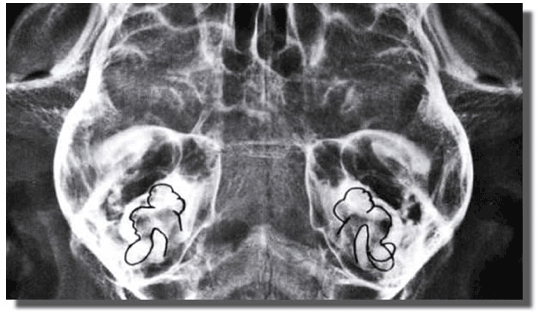

Hay tres canales semicirculares en cada oído, dentro de la porción petrosa del hueso temporal (Figura 5-A), que se denominan de acuerdo a su posición en el espacio (lateral, de orientación horizontal; anterior, de orientación rostro-vertical; y posterior, de orientación caudo-vertical); cada uno de ellos se orienta aproximadamente en un ángulo recto respecto a los otros, correspondiendo uno para cada plano del cuerpo.

Figura 5- A: Representación radiológica del laberinto membranoso en el cráneo de un gato.

Incidencia ventrodorsal. (Tomado de König HE, Liebig HG. Anatomía de los animales domésticos, Tomo 2. Edit. Panamericana. Madrid, España, 2005)